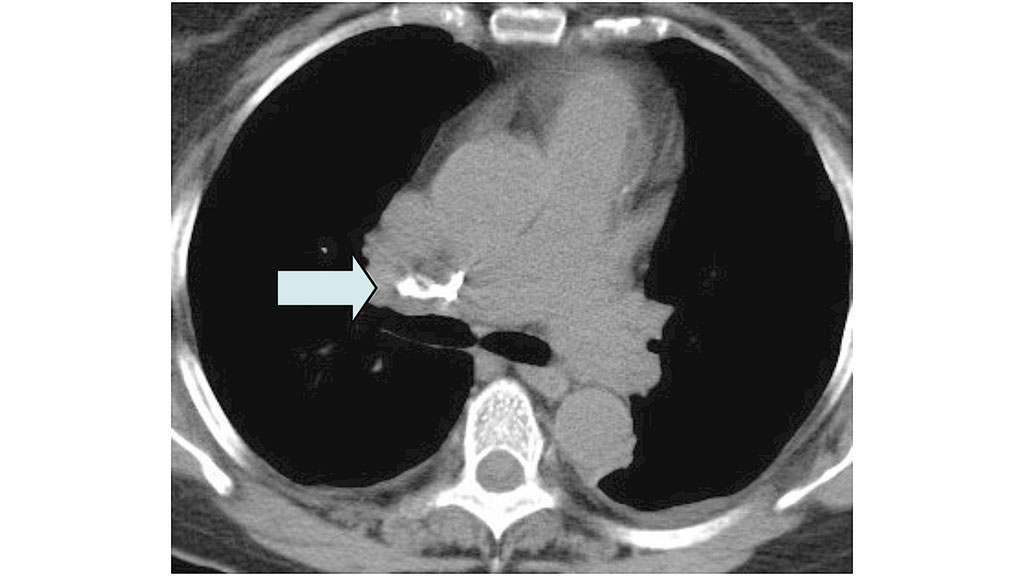

Obwohl die Komplikationsmöglichkeiten im Rahmen des Eingriffes neben den allgemeinen Operationsrisiken der Wirbelsäulenchirurgie (Blutung, Verletzung der Dura und gegebenenfalls des Myelons etc.) teilweise vital bedrohliche Ereignisse wie z. B. ausgeprägte Zementembolien (Abb. 4 bis 6) umfassen, fehlt den Verantwortlichen teilweise die erforderliche Kompetenz, diese Komplikationen zu beherrschen 23 24 25. Trotz der geringen Operationsdauer von durchschnittlich 20 bis 30 Minuten pro Wirbelkörper bedeutet alleine schon die für die Operation erforderliche Bauchlagerung für alte und multimorbide Patienten eine zusätzliche Belastung – in seltenen Fällen kommt es intraoperativ zu Kreislaufstillständen mit Todesfolge, auch wenn Reanimationsmaßnahmen sofort greifen und eine Weiterbehandlung auf einer Intensivstation (kleinere Krankenhäuser verfügen teilweise über keine ITS) gewährleistet ist.